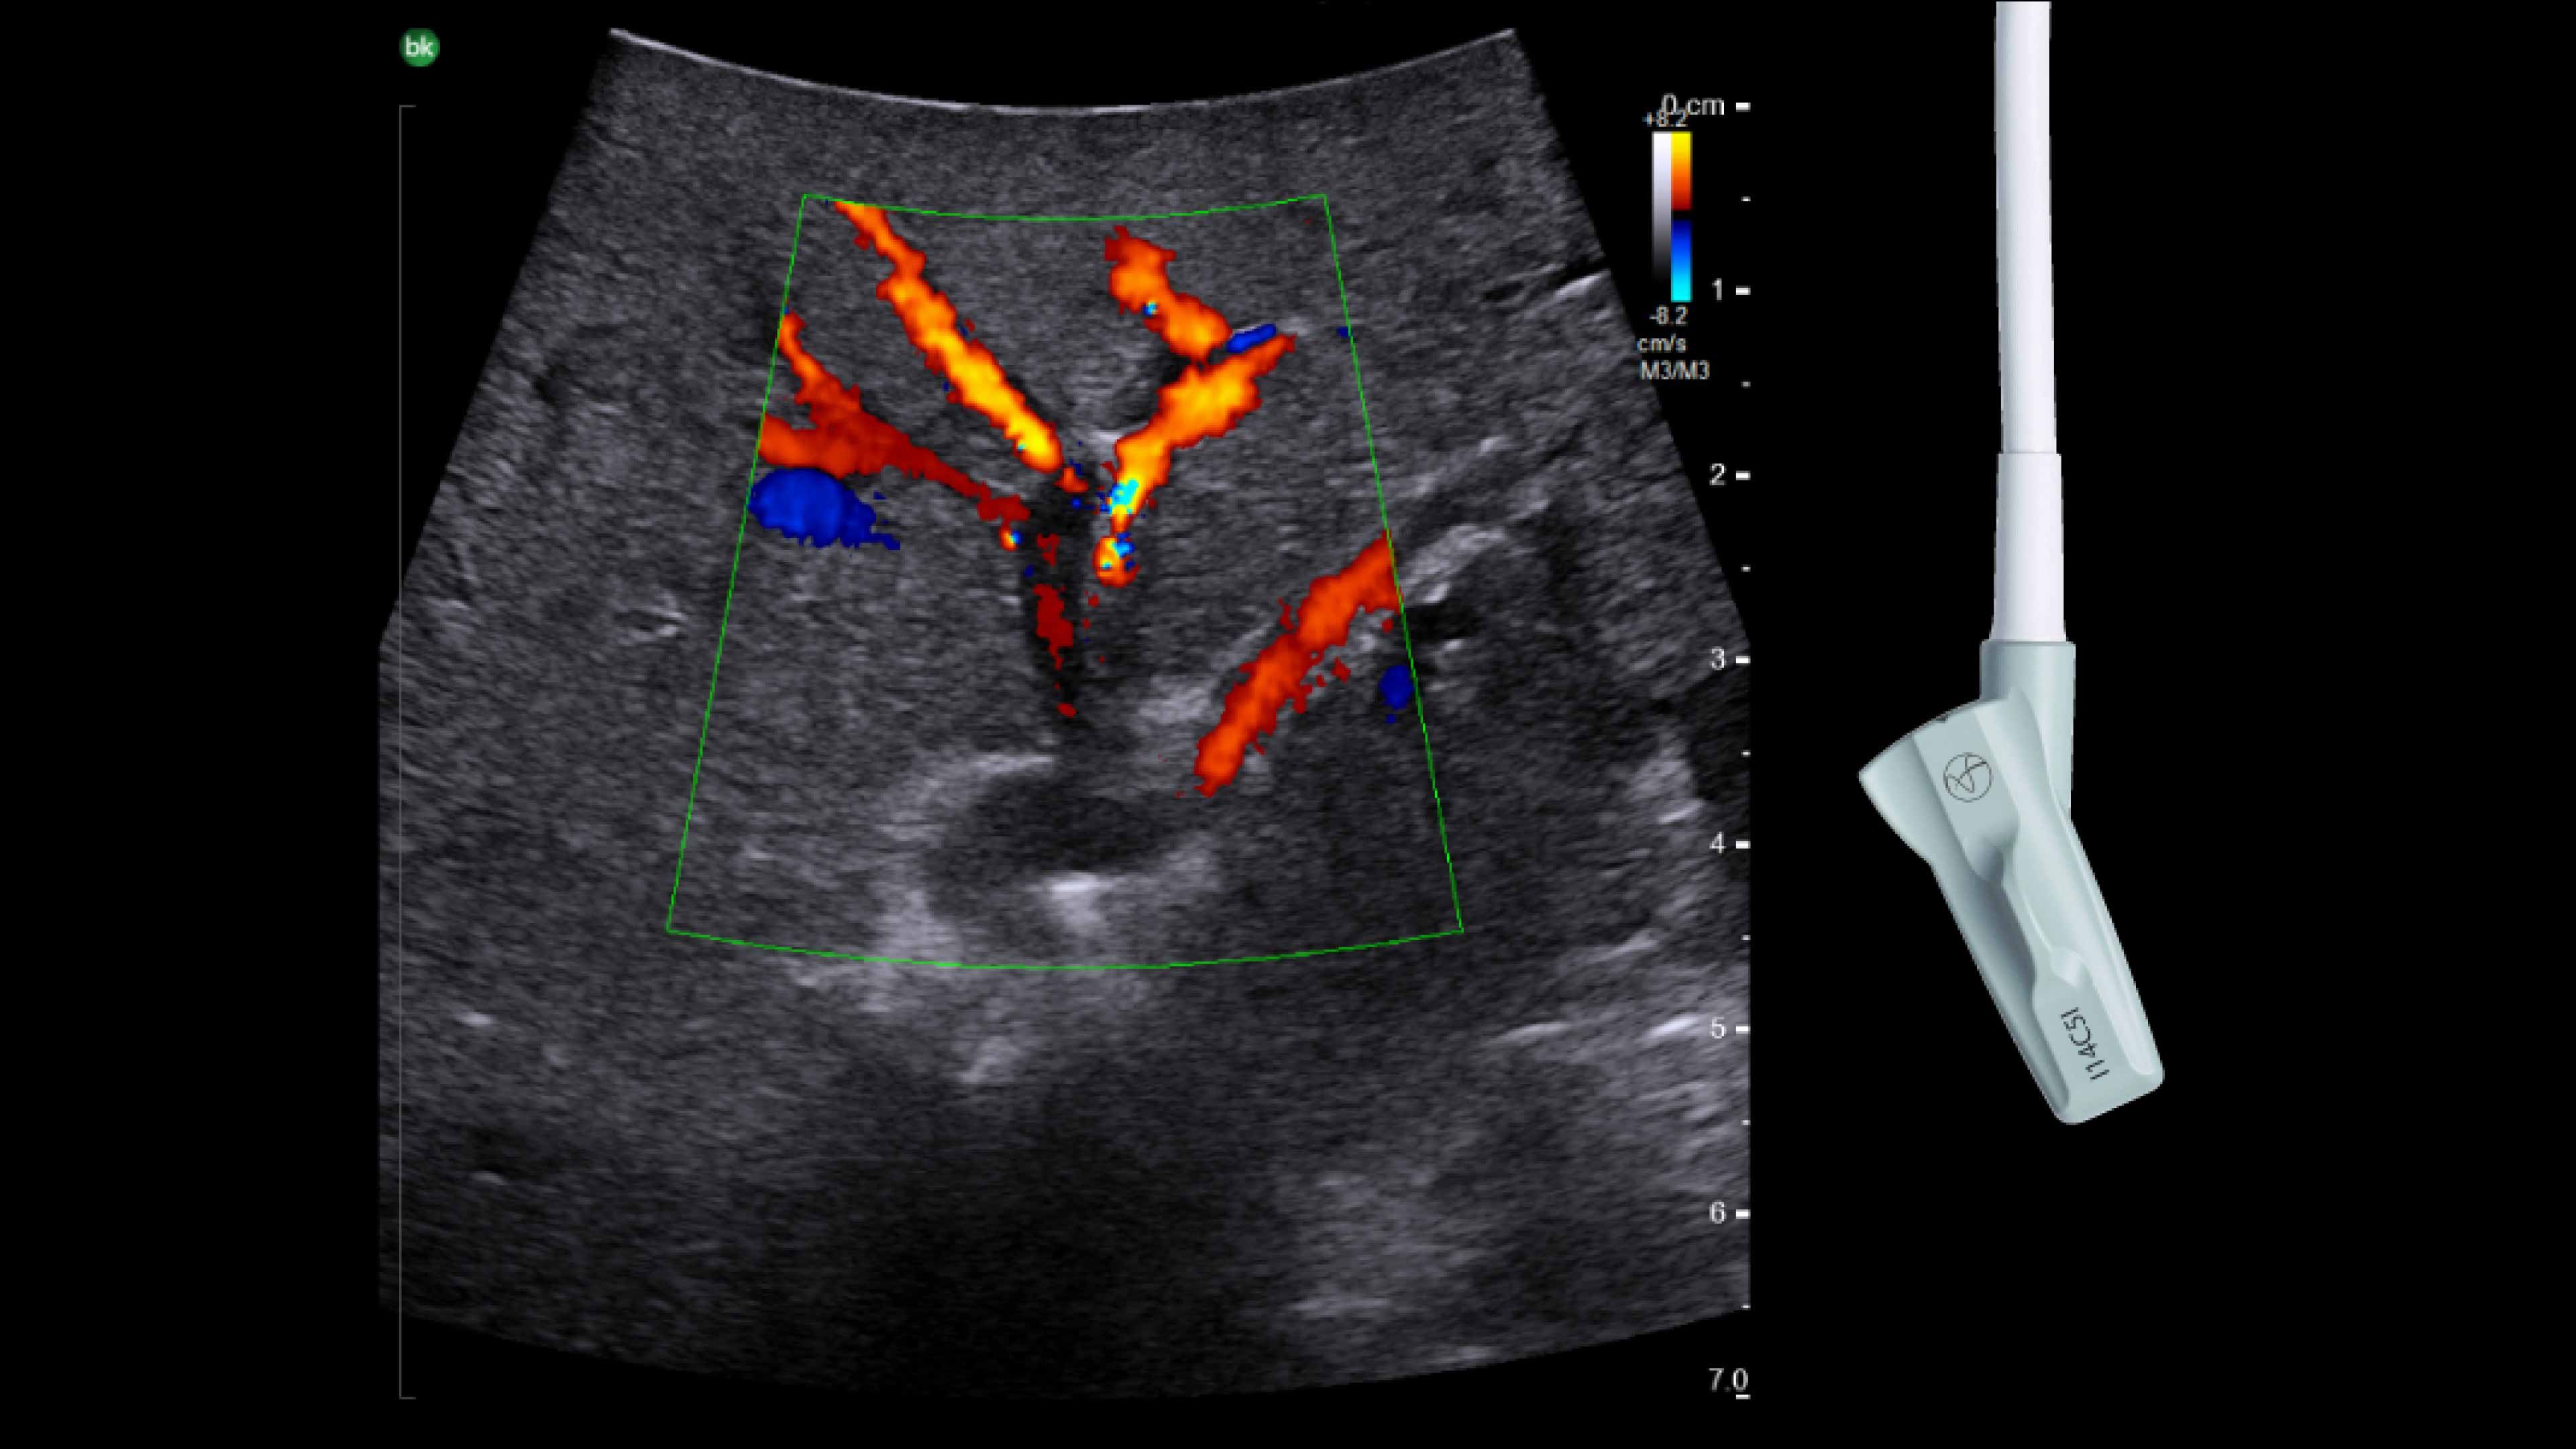

Active imaging supports liver and pancreas ablation procedures by helping you visualize lesions and blood vessels, identify healthy tissue vs. tumor, and guide and view needle placements.

Use intraoperative ultrasound to:

• Enable visualization of disease staging at the time of surgery with excellent image quality.

• Guide and view needle placements in real-time.

• Verify your planned results by assessing pre- and post-ablation images together.

Advanced Laparoscopic Transducer I13C3f*

• Plan and target tumor biopsies and ablations with patented laser technology.

• Achieve preferred insertion angle on up to two needles with proprietary channel design.